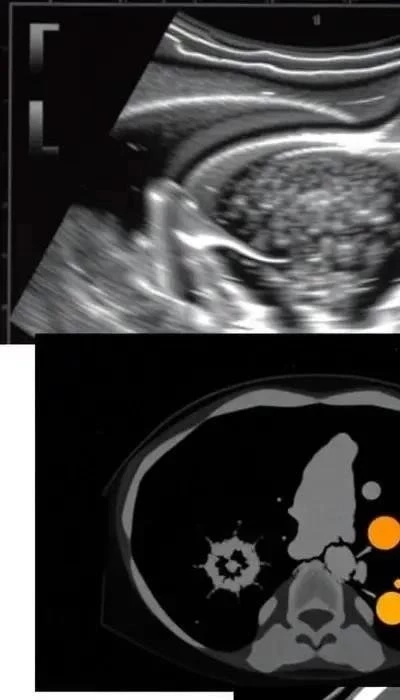

Диагностика рака эндометрия начинается со сбора анамнеза и инструментальных обследований. Современные методы диагностики позволяют выявить опухоль на ранних стадиях, когда симптомы еще отсутствуют. Скрининговая диагностика играет важную роль в раннем обнаружении рака.